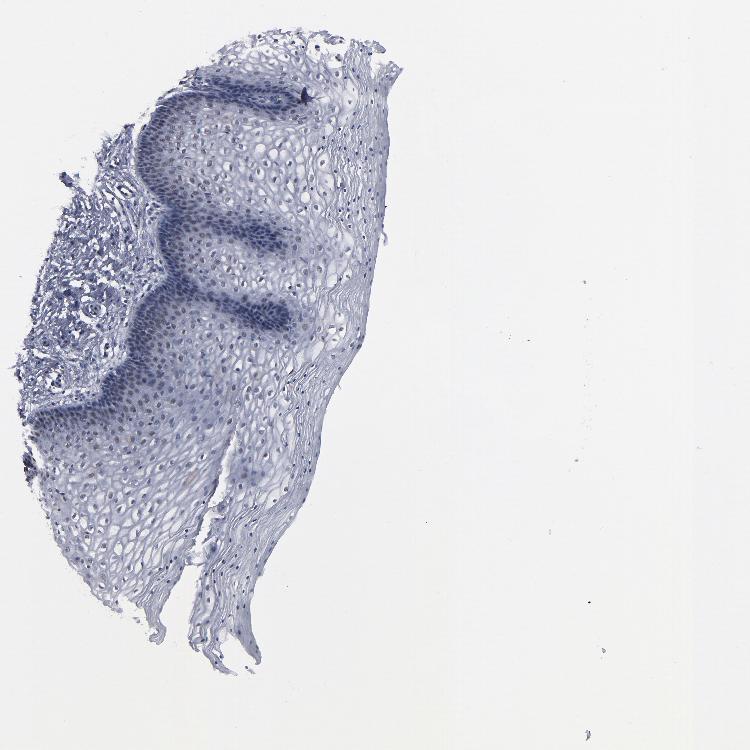

VAGINA - Antibody stainingi

Antibody staining in the annotated cell types in the current human tissue is reported as not detected, low, medium, or high, based on conventional immunohistochemistry profiling in selected tissues. This score is based on the combination of the staining intensity and fraction of stained cells.

Each image is clickable and will lead to virtual microscopy that enables deeper exploration of all samples and also displays staining intensity scores, fraction scores and subcellular localization as well as patient and tissue information for each sample.

Antibody HPA002697

Squamous epithelial cells Not detected